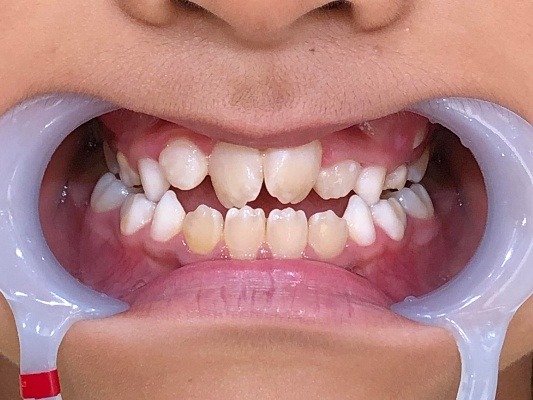

正面

| 治療内容 | インビザライン・ファースト |

|---|---|

| 治療詳細 | 反対咬合や叢生、開咬を整えるために、歯の表面にアタッチメント(白い突起)をつけました。 また、顎間ゴムと呼ばれる引っ掛けるゴムの補助装置も用いて治療を行いました。 |

| 患者情報 | 10代 男性 予防矯正から移行 |

| 主訴 | 受け口 |